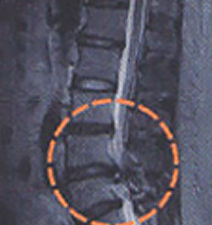

진단

하지직거상검사(下脂直擧上檢査)로 근력감퇴, 감각이상, 슬관절 및 족관절 심건반사에 이상유무를 진단하고 방사선검사 X-ray 및 CT검사로 더욱 정확하고 쉽게 디스크의 진단을 할 수 있습니다.

CT는 종, 횡으로 잘라서 볼 수 있고 신경과 디스크가 서로 다르게 나타나기 때문에 디스크에 의해서 신경이 누른 모습을 직접 볼 수가 있고 조영제를 주입하여 더욱 선명하게 볼 수 있습니다.

MRI는 뼈와 신경, 디스크를 완전히 구분하여 보여주어 목 디스크의 진단을 더욱 세밀하고 쉽게 할 수 있습니다.